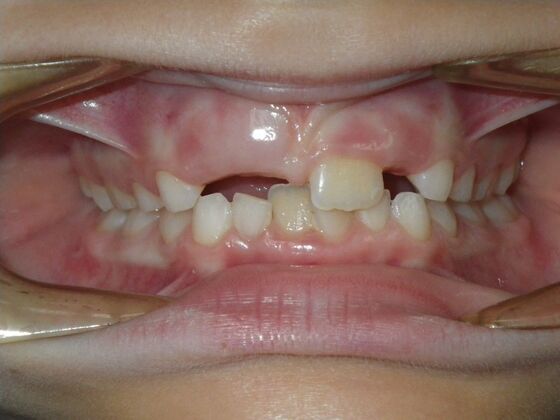

Patient presents with delayed eruption of the upper right central incisor and lower anterior crowding. Treatment plan to include exposure of right central incisor with bracket placement and correction of lower anterior crowding.